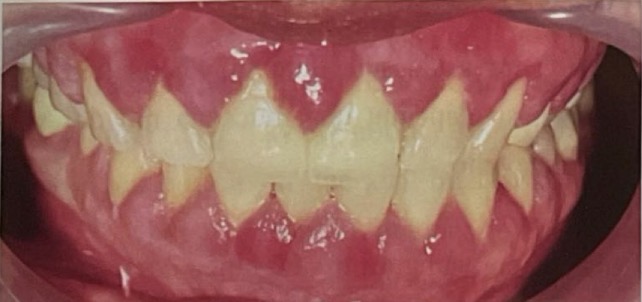

BN CÓ GAI NƯỚU TĂNG SINH, SƯNG TO, CẮNG BÓNG

SỜ DAI, KHÔNG ĐAU, KHÔNG CHẢY MÁU *

CHẨN ĐOÁN

TRIỂN DƯỠNG NƯỚU DO THUỐC PHENYTOIN

TRIỂN DƯỠNG NƯỚU DO DÙNG THUỐC PHENYTOIN

CHẨN ĐOÁN?